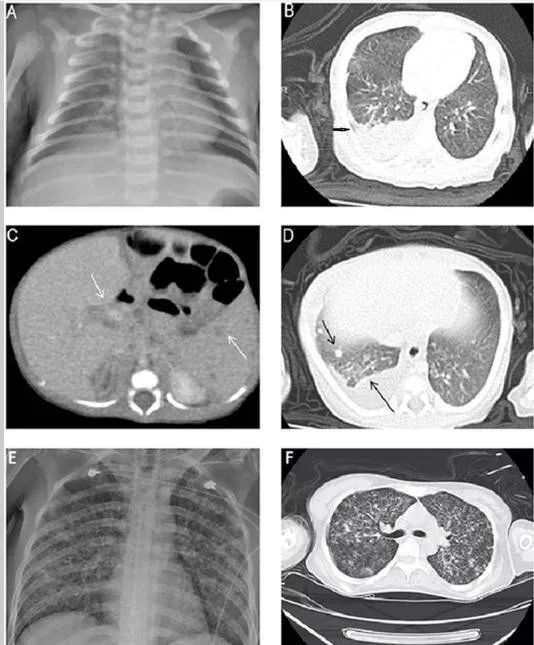

出生后17天:X线胸片右肺野浸润增加(图1A),胸部CT显示婴儿右下叶有大量的右侧胸腔积液和轻微的炎性改变(图1B)。当时,建议进行胸腔积液引流,但他的父母拒绝了。

出生后20天:经父母同意,进行洗胃,洗胃液的三种耐酸染色发现少量的耐酸杆菌。重复进行胸部和腹部CT检查,显示右上肺有斑片状实变,双肺有多个新结节,中度胸腔积液,脾脏和肝门区有多个低密度结节,无肝脏肿大(图1C,D)。随后,进行猪尾导管置入胸腔积液引流术。胸水分析结果显示,白细胞总数为10800/μl,中性粒细胞占6%,淋巴细胞占57%,间皮细胞占37%;总蛋白水平为4.6g/dl,乳酸脱氢酶水平为250IU/L,葡萄糖水平为164mg/dl。怀疑是结核感染。给予异烟肼(15mg/kg/d)、利福平(15mg/kg/d)和吡嗪酰胺(20mg/kg/d)。开始抗结核治疗后,新生儿的症状和体征逐渐消失。

新生儿的母亲是33岁,孕1产1。B组链球菌检测呈阴性。她一直健康,既往没有病史和肺结核接触史;然而,她在分娩后1周出现轻度干咳,出现持续性全身无力,并在产后24天因精神态势改变而住进了我们的ICU。实验室检查显示白细胞增多、血小板减少、凝血障碍、急性肝功能衰竭和急性肾功能衰竭。HIV血清学检测呈阴性。胸片显示粟粒样结核(图1E)。胸部CT显示弥漫性小叶间和小叶内间隔增厚呈毛玻璃样(图1F)。由于当时新生儿高度怀疑有肺结核感染,故对其痰进行抗酸染色和肺结核聚合酶链反应(PCR)。两项检测均呈强阳性。这位母亲立即接受了抗结核治疗,但在住院3天后死亡。痰培养证实结核分枝杆菌感染。